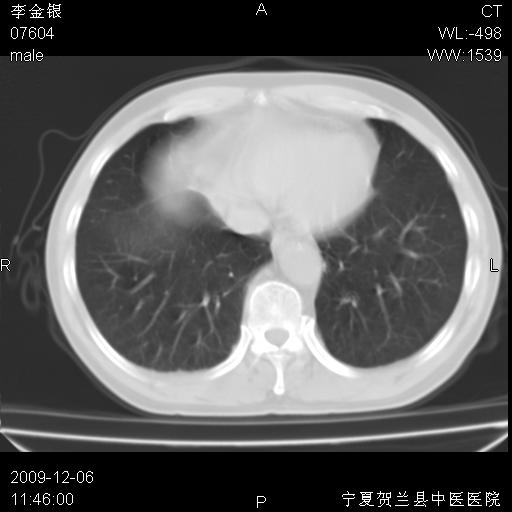

该病人 ,男,62岁,主因咳痰带血两天

考虑右肺中央型占位性病变并阻塞性肺炎.(右肺上叶支气管变窄),建议支纤镜检查.

考虑右肺中心型肺癌伴阻塞性肺炎及右肺门淋巴结转移,建议纤维支气管镜进一步检查。

支气管壁明显增厚 管腔狭窄,腔静脉后多个淋巴肿大,结合年龄病史考虑右肺上叶中央型肺癌并阻塞性肺炎

右肺上叶后段支气管阻塞,右上肺门占位,相应肺段阻塞性肺炎,右肺门有淋巴结肿大。诊断右肺上叶中心型肺癌,阻塞性肺肺炎、右肺门淋巴结转移。

右上叶支气管狭窄,管壁增厚,远端斑片状软组织影,病灶邻近叶间裂,叶间裂无移位。

诊断右肺中央型肺癌。

那个片影应该大部分都是病灶,病灶沿肺段支气管分支生长,后段完全显示不清、闭塞。若为不张应该伴有叶裂的移位,若为炎症应有空气支气管征。

考虑右侧中央型肺癌伴右肺上叶后段阻塞性炎症、肺不张、右肺门和纵隔淋巴结肿大。

右肺上叶中心型肺癌,阻塞性肺炎、右肺门和纵隔淋巴结转移。